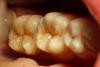

METT Опубликовано 13 апреля, 2013 Автор Поделиться Опубликовано 13 апреля, 2013 Давно не выкладывал-еще фото.46-пломба-дефект-кариес I-II кл медиодистально,на момент обращения у меня фотика не было,пришлось снять только точево и вкладку. Ссылка на комментарий

METT Опубликовано 13 апреля, 2013 Автор Поделиться Опубликовано 13 апреля, 2013 17,на 2-3 снимке на дне sdr Ссылка на комментарий

METT Опубликовано 13 апреля, 2013 Автор Поделиться Опубликовано 13 апреля, 2013 16 Ссылка на комментарий